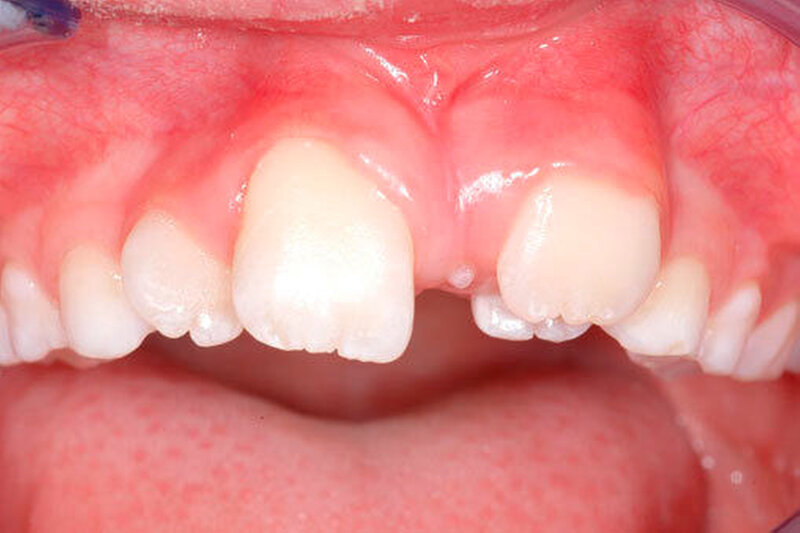

Die Prävalenz überzähliger Zähne wird im Bereich von 0,07 Prozent bis 0,6 Prozent für das Milchgebiss [Luten, 1967; Ravn, 1971; Järvinen Lehtinen, 1981; Magnússon 1984; Skrinjari Barac-Furtinovi, 1991; Yonezu et al., 1997; Chen et al., 2010] und von 0,3 Prozent bis 3,2 Prozent für die bleibenden Zähne [Luten, 1967; Bäckman Wahlin, 2001; Salcido-García et al., 2004; Leco Berrocal et al., 2007; Gündüz et al., 2008; Yagüe-García et al., 2009; Schmuckli et al., 2010; Fardi et al., 2011] angegeben. Die Mehrheit der überzähligen Zähne im Milchgebiss sind seitliche Schneidezähne im Oberkiefer, die meist mit einer normalen Morphologie und Lage durchbrechen (Abbildungen 1 bis 3) [Luten, 1967; Humerfeld et al., 1985; Garvey et al., 1999; Ferrés-Padró et al., 2009]. Der oft ungestörte Durchbruch und das Ausbleiben von Symptomen führen dazu, dass überzählige Zähne in der Milchdentition oft gar nicht diagnostiziert werden, und dies wird auch als Erklärung für die unterschiedlichen Prävalenzen überzähliger Zähne im Milch- und bleibendem Gebiss angeführt [Wang Fan, 2011]. Überzählige Zähne sind häufiger bei Männern als bei Frauen, wobei über ein Verhältnis von 1,18:1 bis 4,5:1 berichtet wird [Rajab Hamdan, 2002; Fernández Montenegro et al., 2006; Gündüz et al., 2008; Wang Fan, 2011]. In der Schweiz publizierten von Arx (1990) und Schmuckli und Mitarbeiter (2010) Geschlechterverhältnisse von 2,6:1, beziehungsweise 2,75:1. In einer aktuellen Arbeit von Mossaz und Mitarbeiter (2014) von Patienten aus dem Raum Bern lag dieses Verhältnis etwas ausgeglichener bei 1,61 zu 1.

Die überzähligen Zähne mit identischer Zahnform finden sich normalerweise beim oberen seitlichen Schneidezahn. Zusätzliche Prämolaren und Molaren können aber auch auftreten. Die Mehrheit der überzähligen Zähne im Milchgebiss sind vom identischen Zahnform-Typ und bleiben nur selten impaktiert oder retiniert.